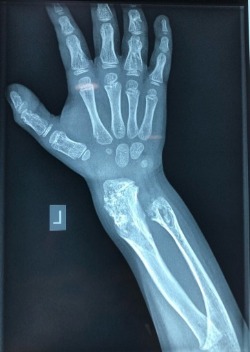

• Γάγγλιο, καλοήθης κύστη γεμάτη με διαυγές κολλώδες υγρό που εξορμά από παρακείμενη άρθρωση (συνήθως την άρθρωση του καρπού) και μπορεί να επηρεάζει την κίνηση των αρθρώσεων ή να προκαλεί πόνο.  Θεραπεύεται με αφαίρεση εάν και εφόσον προκαλεί  συμπτώματα.

Η εικόνα απεικονίζει περιστατικό με παρουσία γάγγλιου, όπου πραγματοποιήθηκε αφαίρεση του απο τον Δρ. Ζένιο.